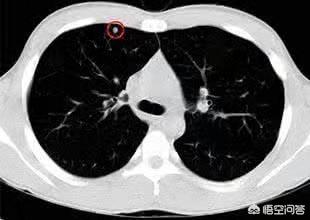

Les nodules pulmonaires sont classés en différents types en fonction de leur densité. Les nodules de densité plus élevée, qui apparaissent comme des points blancs sur le scanner thoracique, sont appelés nodules solides, tandis que les nodules en verre dépoli sont plus légers et ressemblent à de la vapeur d'eau sur le verre. Les nodules en verre dépoli, en particulier les nodules en verre dépoli pur, ont tendance à être plus malins.

Pour la définition du nodule pulmonaire, la directive médicale chinoise indique : L'imagerie (scanner thoracique) montre une ombre pulmonaire solide ou sous-solide focale, arrondie, de densité accrue, d'un diamètre ≤3 cm, qui peut être isolée ou multiple, et qui n'est pas accompagnée d'atélectasie pulmonaire, d'hypertrophie des ganglions lymphatiques hilaires et d'épanchement pleural.

D'une manière générale, toute ombre de densité accrue dans les poumons d'un diamètre inférieur à 3 cm est appelée nodule pulmonaire. Le degré de risque n'est pas seulement lié à la taille, mais doit également être déterminé en fonction de la morphologie, de la densité et de la vitesse de multiplication du nodule.

Avant la tomodensitométrie, la probabilité de détecter un nodule pulmonaire était inférieure à 0,2 %, et la taille du nodule trouvé était généralement supérieure à 1 cm. Avec la popularité de la tomodensitométrie, la probabilité de détecter un nodule pulmonaire a considérablement augmenté, mais la question de savoir quelle taille ou quel type de nodule pulmonaire est le plus dangereux est un sujet particulièrement préoccupant à l'heure actuelle.

Premièrement, pour la division des nodules pulmonaires, les nodules pulmonaires ≥8 mm et ≤3 cm sont actuellement appelés nodules pulmonaires typiques, tandis que seuls les nodules pulmonaires <8 mm sont appelés petits nodules !

Deuxièmement, il existe une corrélation entre la taille du nodule pulmonaire et le degré de risque de bénignité ou de malignité ! En général, on considère que les nodules pulmonaires de moins de 5 mm ont un risque de malignité de 0 à 1 % ; ceux de 5 à 10 mm ont un risque de malignité de 6 à 28 % ; et ceux de plus de 20 mm ont une probabilité de malignité beaucoup plus élevée, de près de 60 % ou plus, ce qui est similaire au degré de malignité des nodules pulmonaires de type verre dépoli !